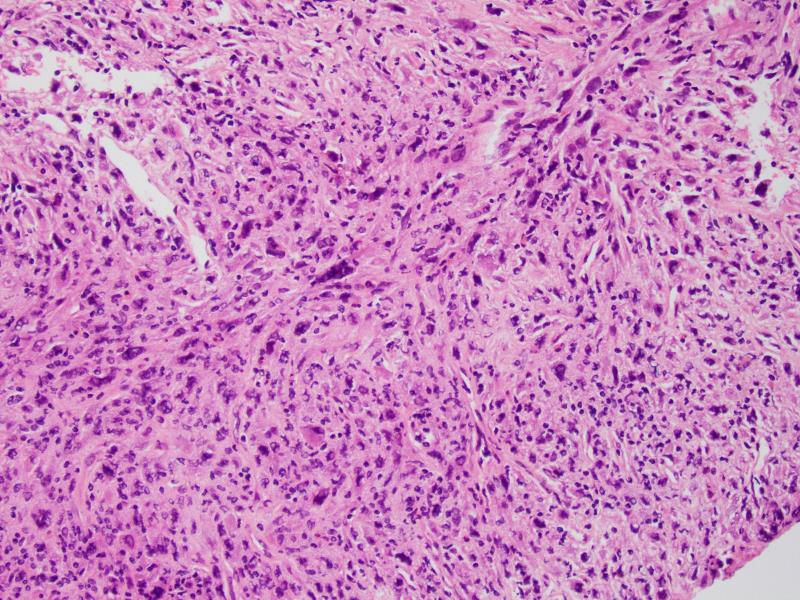

镜下见肿瘤由异型性明显的圆形、多边形深嗜酸性的细胞和一些小的未分化细胞及梭形细胞混合组成;

有些病例见梭形细胞呈束状或不规则状排列,偶尔可呈席纹状排列;部分病例还可见血管外皮瘤样排列;

部分细胞呈蝌蚪状、带状或网球拍状,胞质呈深嗜伊红色,外形不规则,一些细胞大而畸形,具深伊红色胞浆,这类细胞具有诊断价值;

部分区域可见瘤巨细胞或多核巨细胞,类似多形性未分化肉瘤;

肿瘤内常见坏死灶,核分裂象活跃。